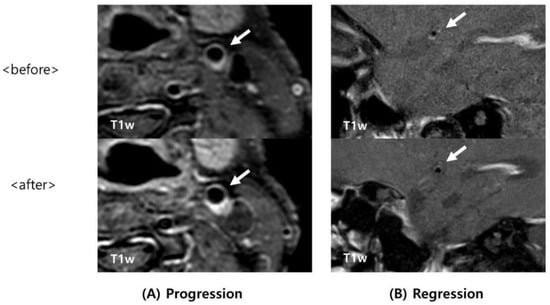

| Intraplaque hemorrhage (IPH) Progression of IPH | 13 (37.1) 1 (2.9) | 7 (100) 6 (85.7) | 0.003 <0.001 |